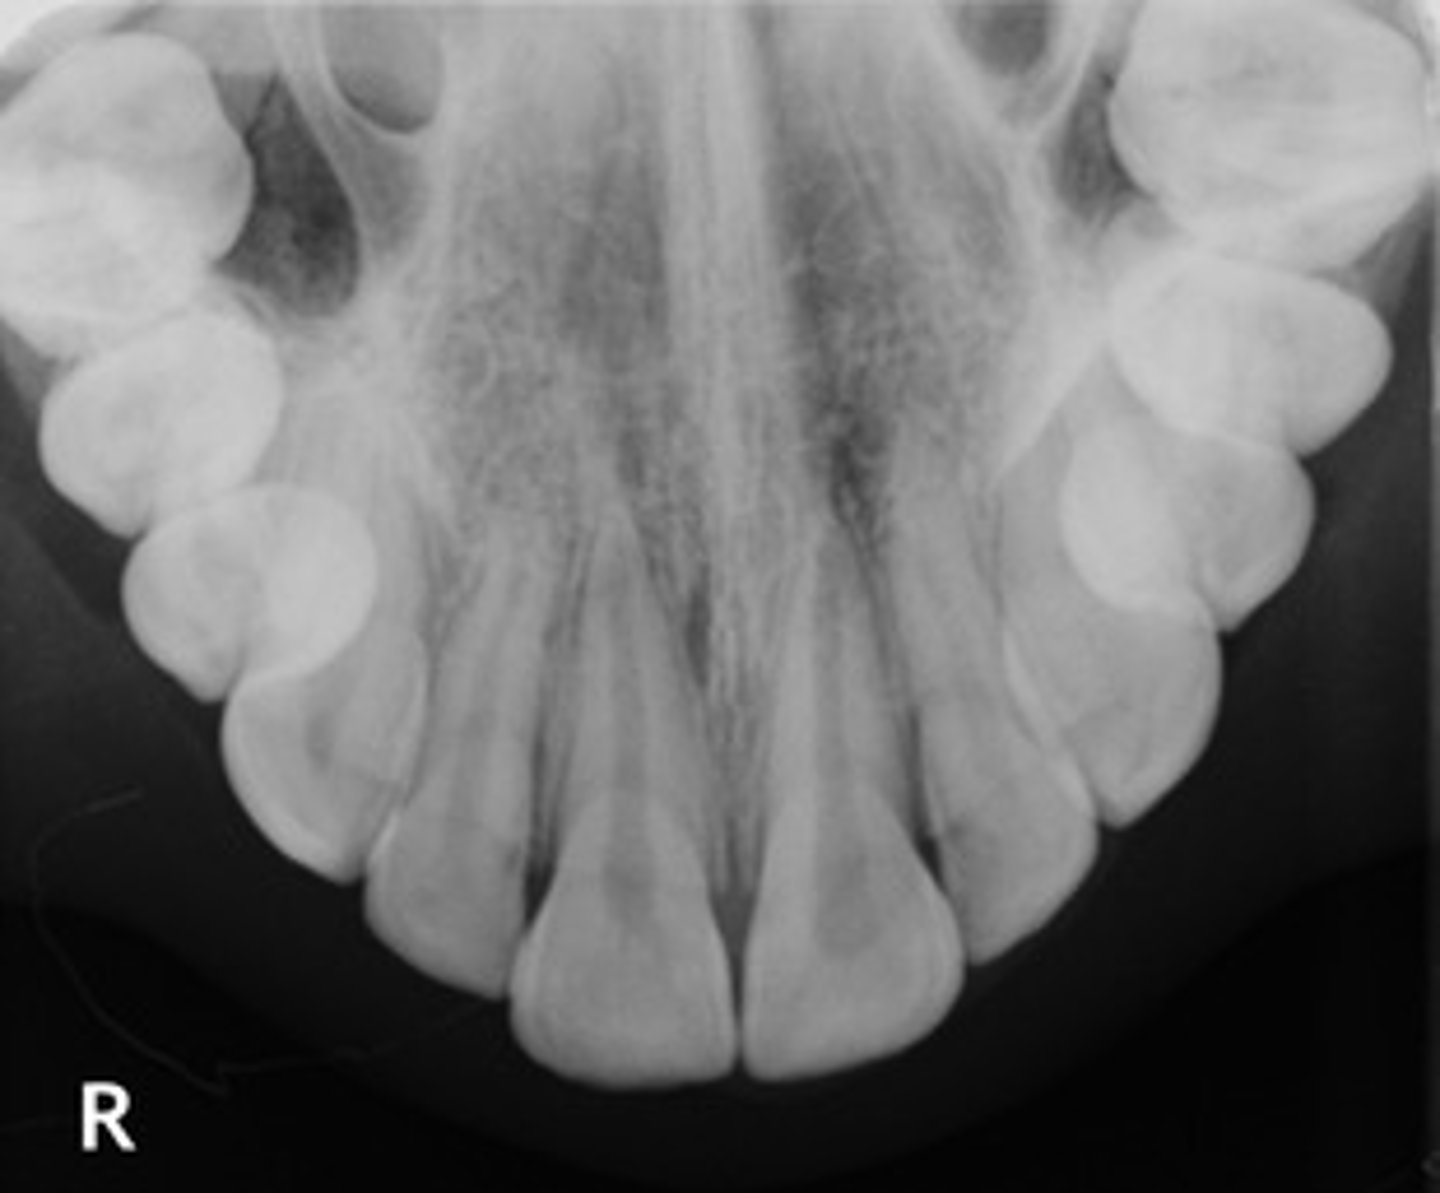

Identify if this is a:

A. Panoramic

B. Cross-sectional image

C. Periapical

D. Bitewing

E. Occlusal

E

describe the general orientation or relationship of an object to an occlusal

Large film placed on occlusal surfaces

Shows large areas

Used when PA is not possible